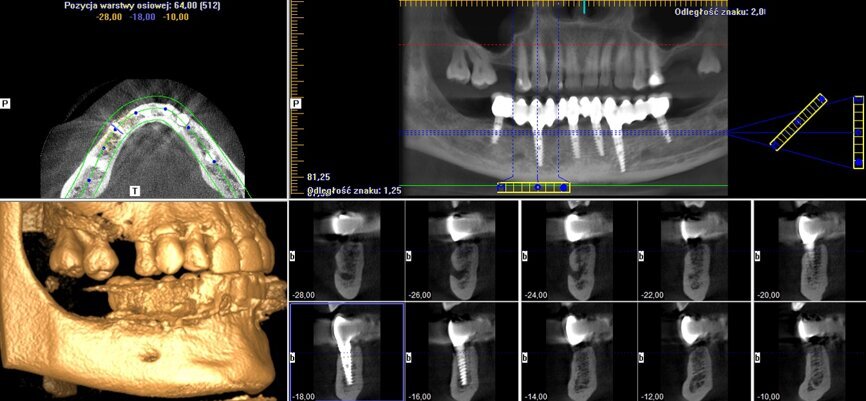

Implanty zostały wprowadzone wg zasady przylegania w cieniu, tzn. wszczep musi na całej swojej długości mieć kontakt z którąś ze ścian zębodołu 1-2 mm subkrestalnie (Ryc. 4). W przypadku konieczności użycia membrany, musi ona mieć możliwość rozpostarcia się nad ubytkiem kostnym i implantem tak, aby odległość pomiędzy membraną a wszczepem nie była mniejsza niż 2 m (Ryc. 3). Wszczepy o

charakterystyce agresywnej wprowadzono w okolice zębów: 36, 34, 32, 42, 44 i 46.

przygotowanej wcześniej protezie czasowej metodą bezpośrednią. Czasowe uzupełnienie protetyczne osadzono, używając cementu tymczasowego (Ryc. 5 i 6). Zlecono wykonanie zdjęcia techniką CBCT (Ryc. 7). Wizytę kontrolną wyznaczono następnego dnia, a szwy zostały usunięte po 10 dniach.

zlecono też wykonanie kontrolnego zdjęcia CBCT i następnego po 12 miesiącach (Ryc. 10 i 11).